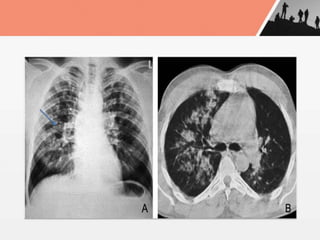

Chest xray in HAPO

- peripheral patchy pulmonaryedema in lower zone